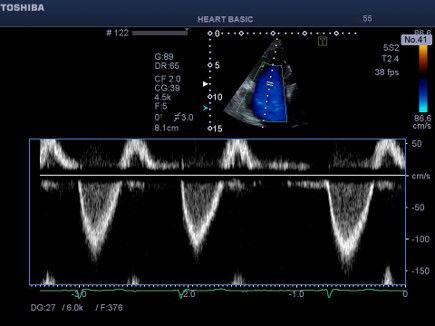

Εικόνα 3 .Παλμικό Doppler στο άκρα των γλωχίνων της τριγλώχινας . Το

σήμα της ανεπάρκειας έχει γραμμική ροή (ελεύθερη ανεπάρκεια). Η

μέγιστη ταχύτητα της ανεπάρκειας τριγλώχινας είναι 1,3 m/s που

αντιστοιχεί σε κλίση πίεσης 5 mmHg . Η δεξιά κοιλία δεν «γεννά πίεση» και

υπάρχει εξισορρόπηση πιέσεων μεταξύ πνευμονικής αρτηρίας, δεξιάς

κοιλίας και δεξιού κόλπου θυμίζοντας τη φυσιολογία της «επέμβασης

Fontan με συστηματική αριστερή κοιλία». Λόγω αύξησης των

πνευμονικών αντιστάσεων, δηλαδή λόγω αυξημένου μεταφορτίου της

δεξιάς κοιλίας, εμφανίζεται δεξιά καρδιακή ανεπάρκεια με χαμηλή

καρδιακή παρόχή με φυσιολογ ί α ομοιάζουσα με την « failing Fontan ».